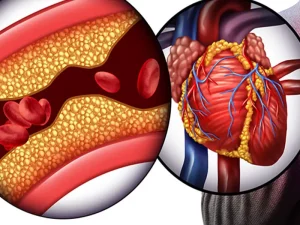

درمان بیماری گرفتگی عروق کرونر بسته به نوع گرفتگی میتواند بدون درد یا عمل باشد و با تغییراتی در سبک زندگی مانند ترک سیگار، داشتن

آنژین قلبی در واقع زمانی که خون به قلب نرسد اتفاق می افتد، هر فردی ممکن است با این مشکل قلبی مواجه شود که از

گرفتگی رگ های قلب میتواند بسیار خطرناک بوده و عوارض جبرانناپذیری را برای بدن بهدنبال داشته باشد. زیرا قلب یکی از پراهمیتترین و حساسترین ارگانهای